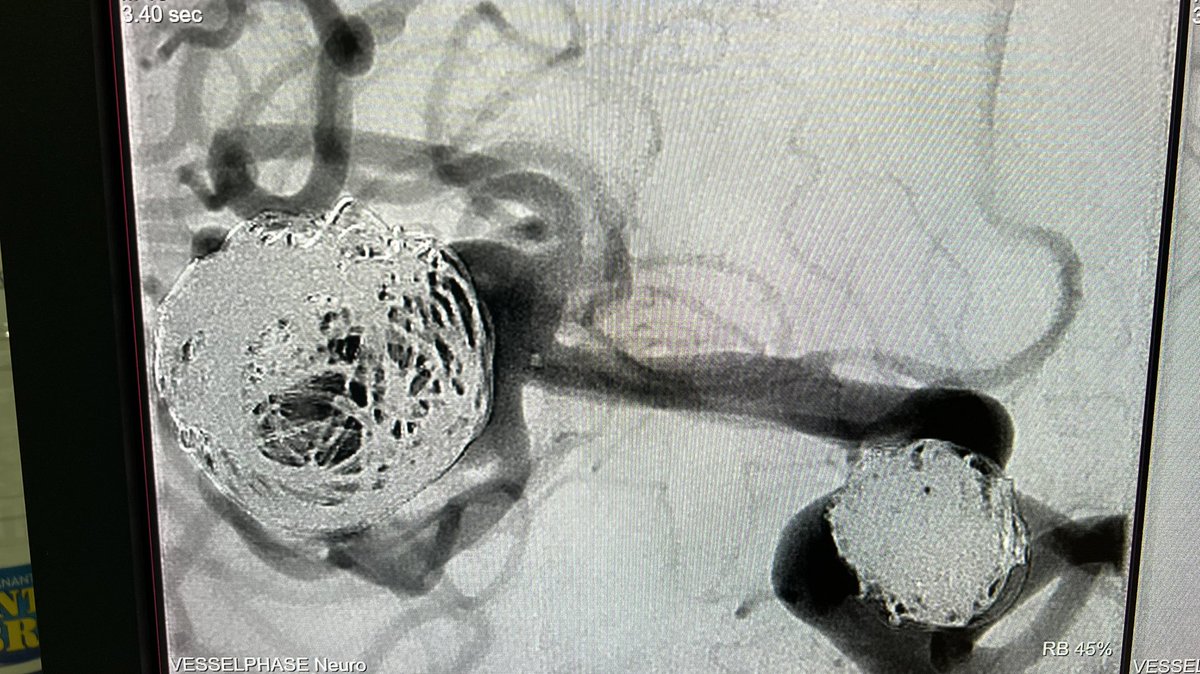

Case of the day. Fetal PcomA aneurysm. Endovascular treatment, jailing with Contour intrasacular device + coils. #neuroradiology #endovascular #aneurysm #embolization #intrasacular